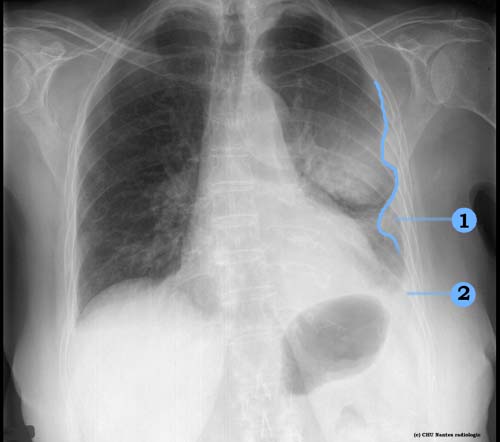

Masses pleurales

1 . masses pleurales : opacité périphérique s'appuyant sur la paroi thoracique avec un raccordement en pente douce et à limite interne nette

2 . épanchement pleural gauche associé